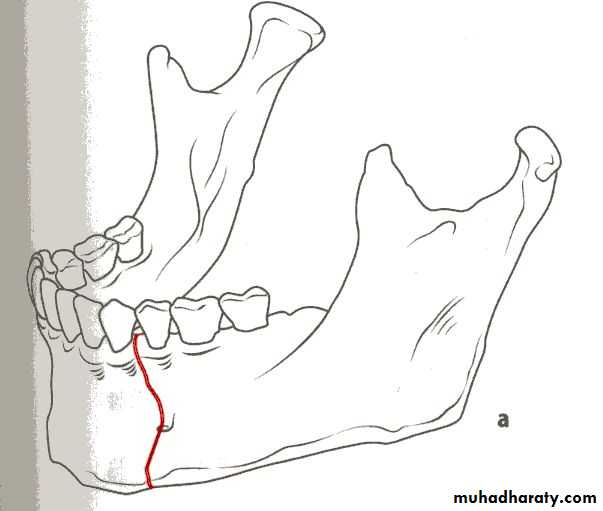

1- Horizontally favorable fracture.

2- Horizontally unfavorable fracture.

When the muscle pull resist fracture displacement , it is favorable(undisplaced), but, when the muscle pull distract the fragments away from each other resulting in displacement , it is unfavorable.

• Horizontally unfavorable fracture extends from the upper border downwards and backwards.

• Horizontally favorable fracture extend from upper border downwards and forwards.